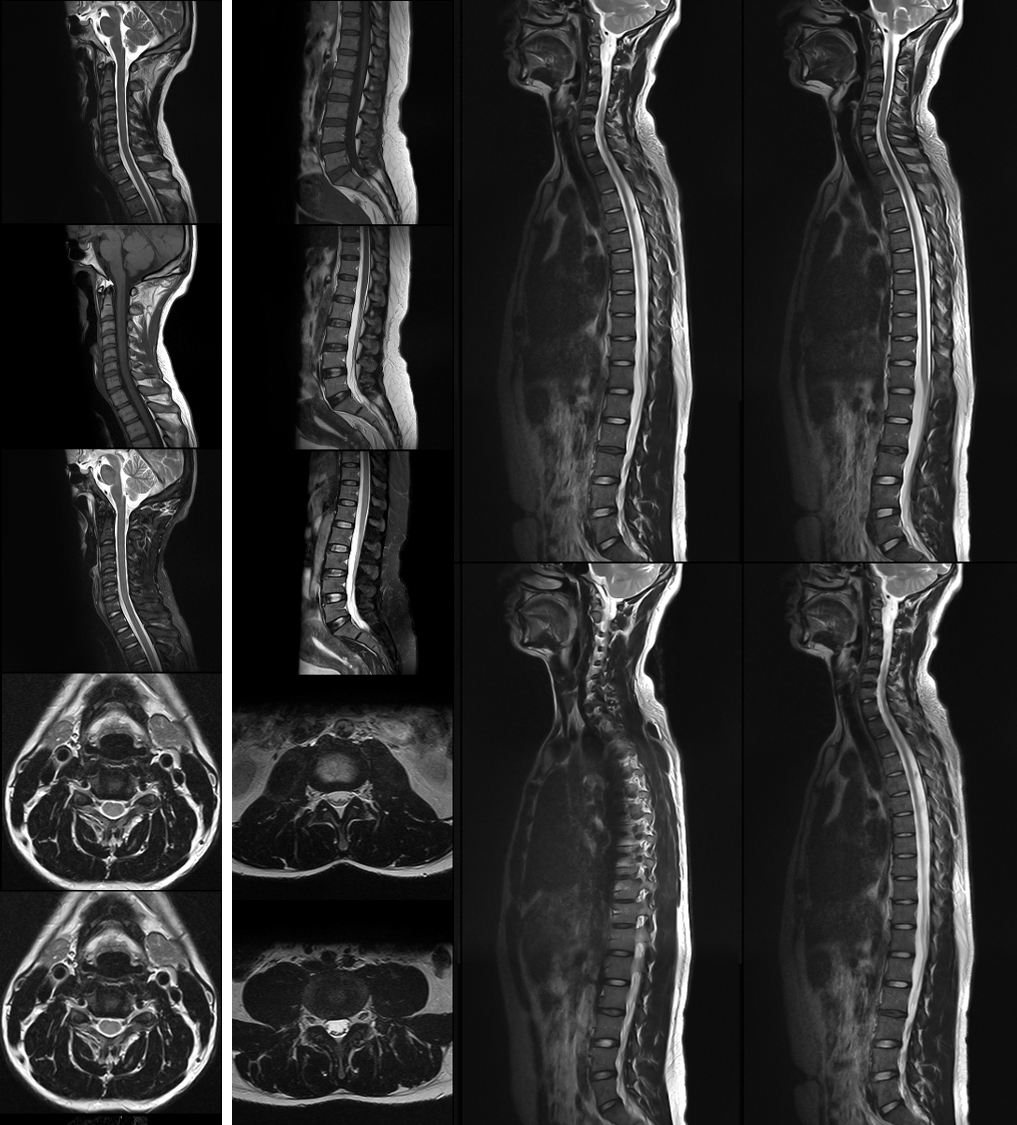

MR

頸椎、腰椎、全脊柱

-

醫療科技事業部